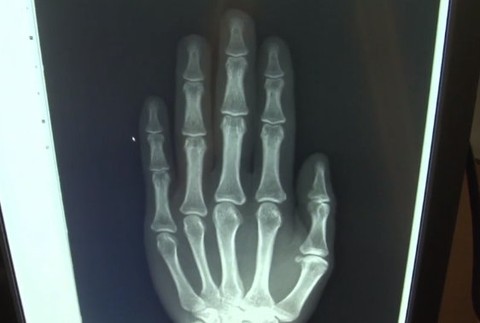

Podľa zamestnancov zariadenia je však častejším problémom ako ochorenie to, že maloletí klamú o svojom skutočnom veku. Aj dvoch Sýrčanov museli najprv poslať na určenie takzvaného kostného veku.